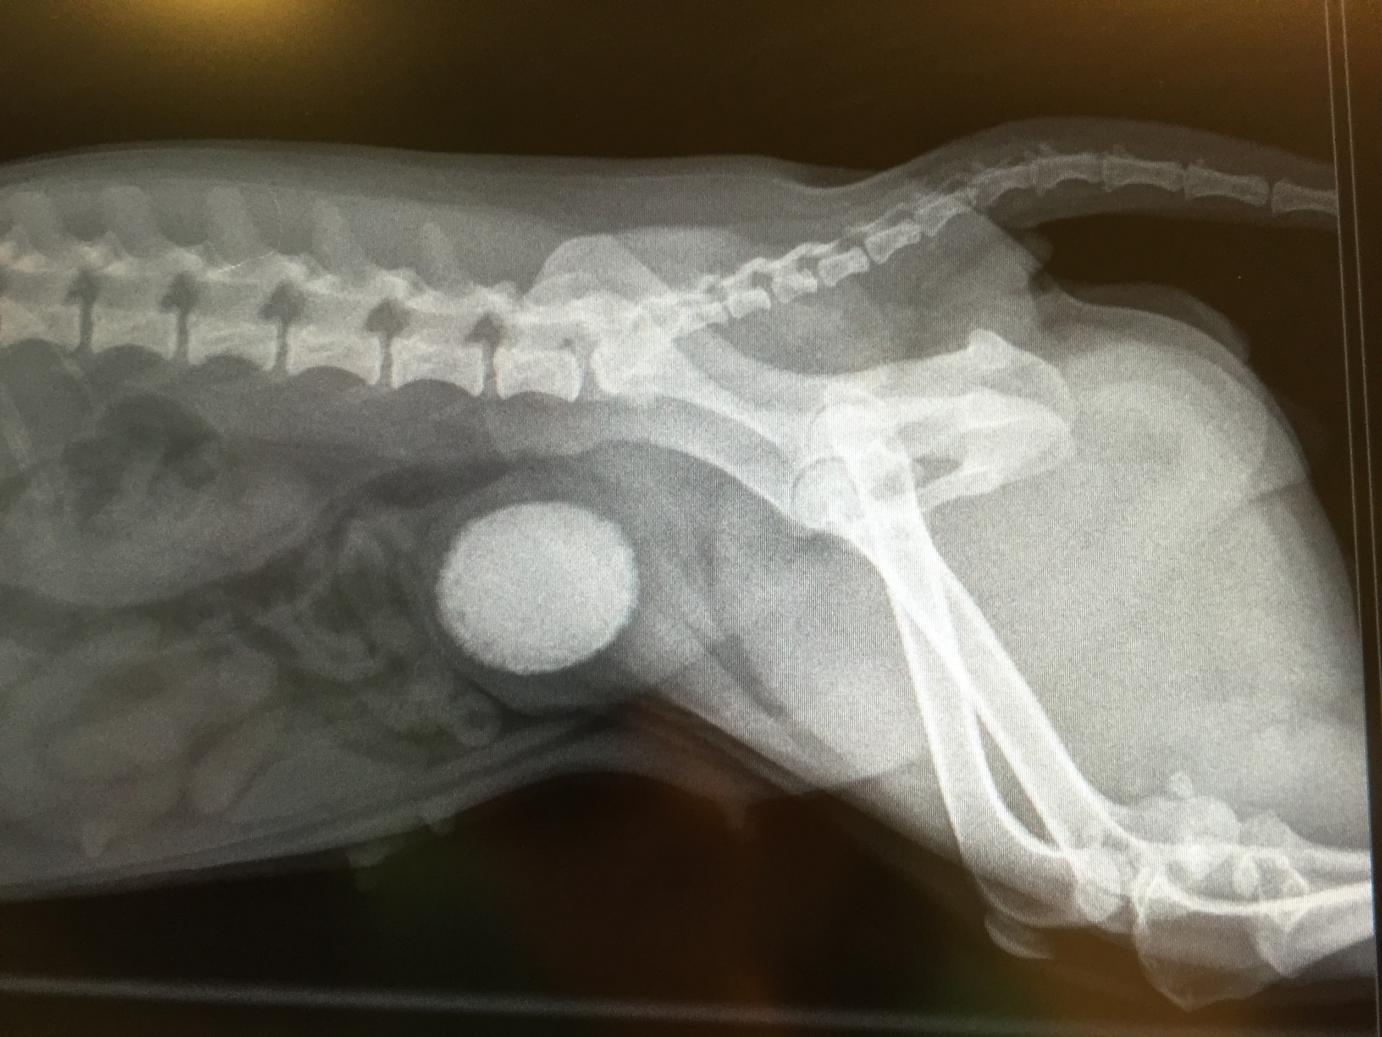

BlæreTrille er en skøn og charmerende lille blandingshund, som i perioder havde haft lidt blod i sin urin samt ændret ædfærd, idet hun ikke virkede så tilpas som tidligere.

Hun blev indlagt til undersøgelse, og allerede ved den kliniske undersøgelse kunne vi konstatere, at hendes blære føltes usædvanlig fast.

Et røntgenbillede afslørede årsagen - i hendes blære lå en kæmpestor sten!

Trille blev opereret, og stenen blev fjernet fra hendes blære.

Efterfølgende blev stenen, der målte 4 cm i længde, sendt til nærmere analyse på et laboratium, så dens præcise mineralsammensætning kunne blive afgjort. Dette har nemlig betydning for, hvilket foder Trille skal have fremadrettet for at undgå, at der danner sig en ny sten i hendes blære.